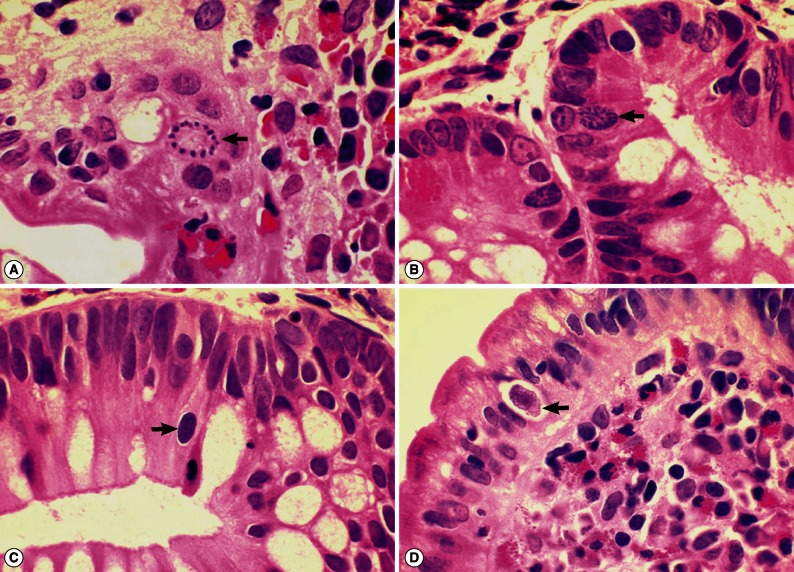

Isospora belli Infection with Chronic Diarrhea in an Alcoholic Patient

The Korean Journal of Parasitology 2013;51(2):207-212.